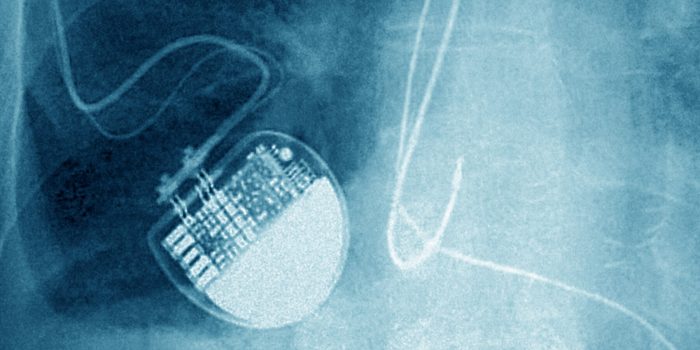

The heart devices do not track location, nor do they transmit across large distances.